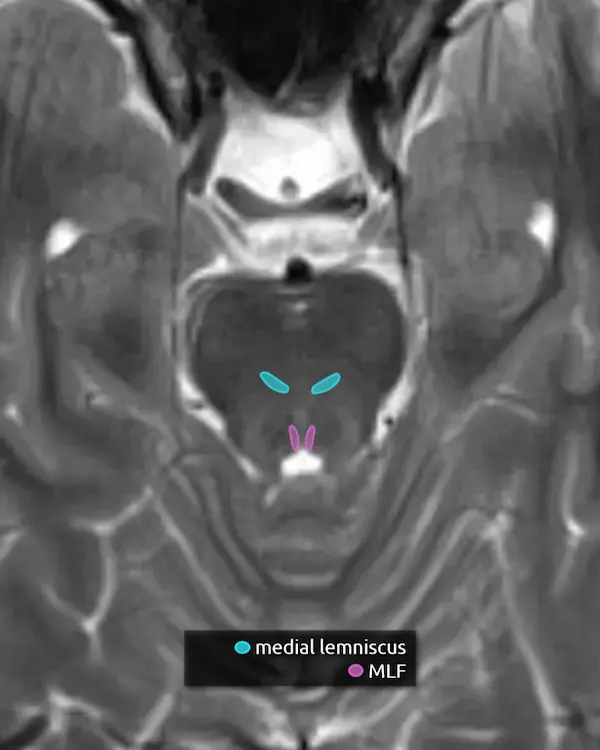

5. Medial lemniscus

The medial lemniscus is an ascending sensory pathway that spans the entire brainstem, originating at the nucleus gracilis and cuneatus (see level 5) in the medulla and ending at the primary sensory nucleus of the thalamus: the ventral posterolateral nucleus (VPL). It begins medially in the medulla and becomes more lateral at the level of the midbrain, located in close proximity to the substantia nigra. It is responsible for vibration sensation, fine touch, and proprioception.

Lesions involving the medial lemniscus may cause contralateral loss of vibration sensation and joint position sensation on physical exam with symptoms of numbness and paresthesias.

6. Medial longitudinal fasciculus (MLF)

The MLF is an ascending and descending pathway responsible for coordinating eye movements. It connects all of the cranial nerve nuclei that innervate the extraocular muscles (CN III, IV, and VI) as well as the vestibulocochlear nuclei (CN VIII). The MLF spans the entire brainstem, however lesions producing visual symptoms will probably be in the midbrain or pons.

There are characteristic syndromes that result from damage to the MLF, most commonly internuclear ophthalmoplegia (INO) or INO-plus syndromes. A common clinical scenario is a patient with multiple sclerosis who develops a demyelinating lesion along the MLF in the midbrain or pons and presents with bilateral INO.